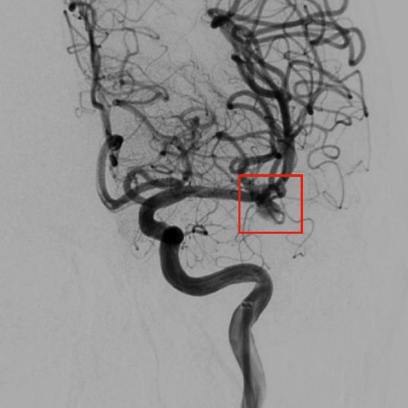

植入装置后动脉瘤腔内血流瘀滞明显减轻。